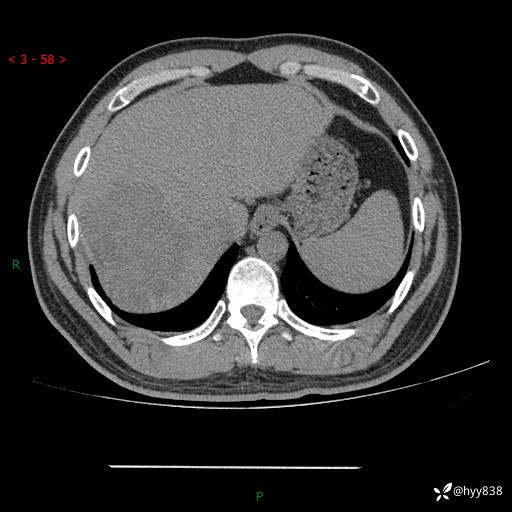

患者性别:男

患者年龄:29岁

简要病史:外院超声提示肝脏占位性病变

辅助检查:CT

临床诊断:肝占位

肝脏CT平扫